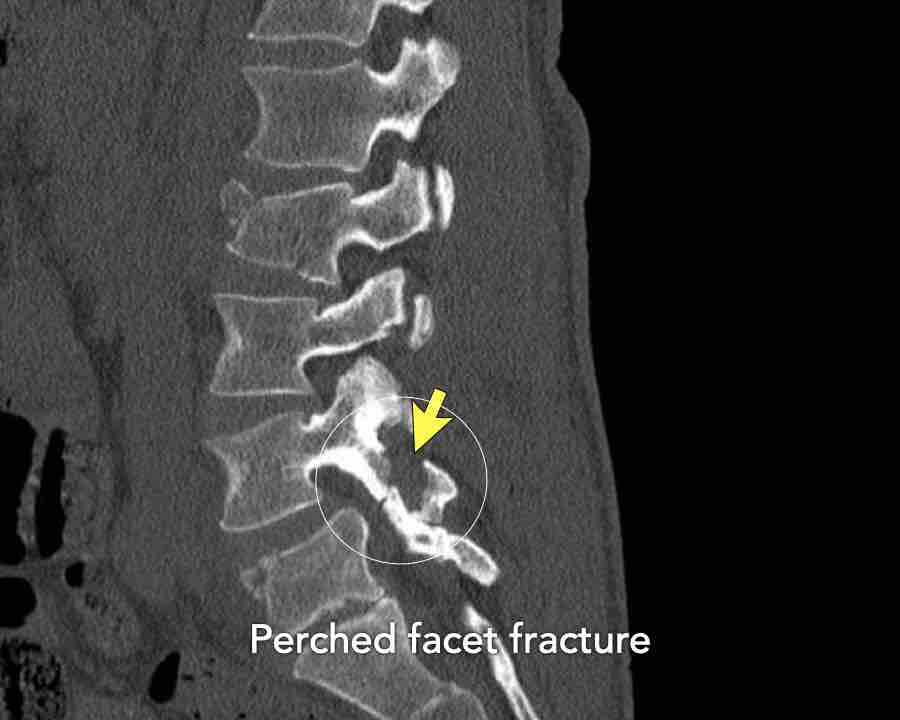

What are the findings?

What is the highest AO-type of injury?

Findings

- Dislocation of the proximal vertebrae anteriorly (white arrow).

- Both facet joints are perched (black arrows). Perched means to be situated above or on the edge of something. In this case the inferior process of vertebral articular joints appears to sit on the ipsilateral superior articular process of the vertebra below.

- Due to the anterior displacement a fracture of the spinous process is seen, in a horizontal oblique course.

Conclusion

Type C injury.